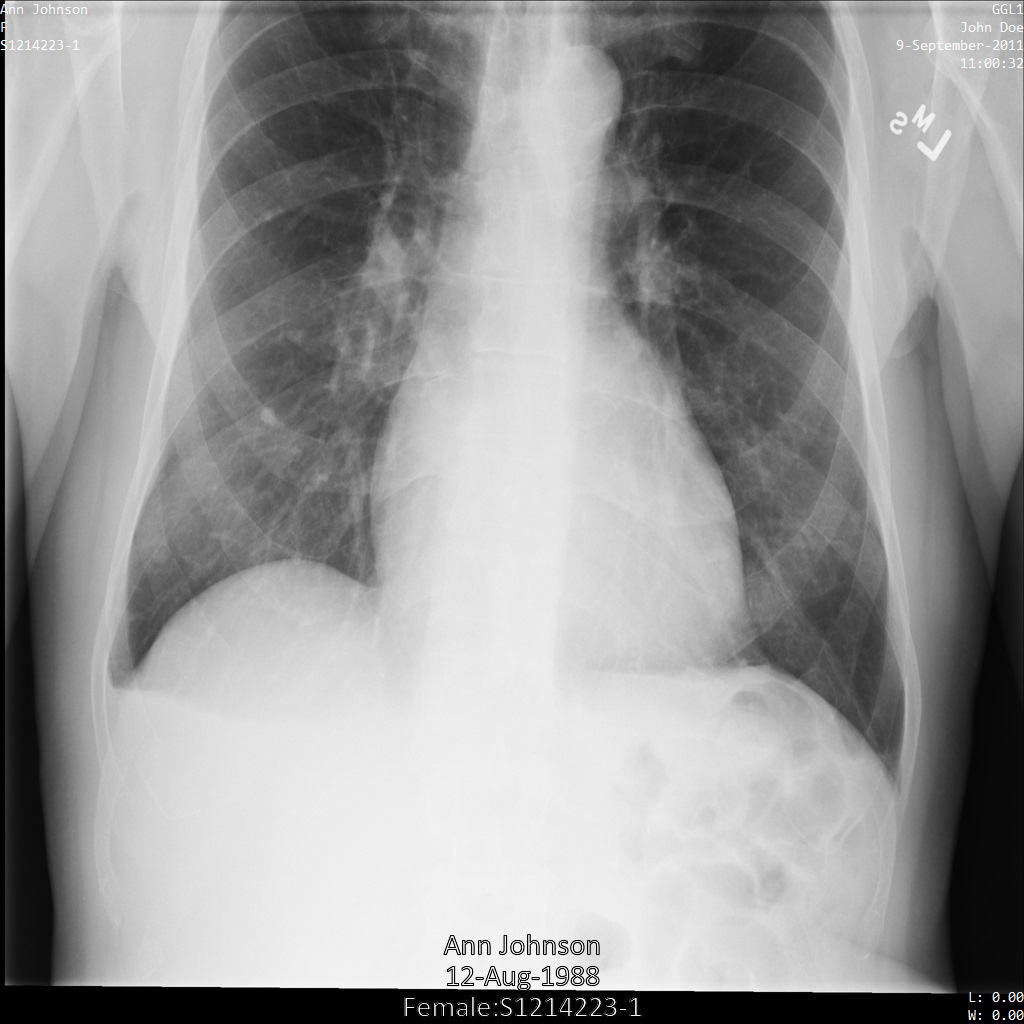

以下各部分提供的示例展示了如何使用各种方法对 DICOM 数据进行去标识化。每个示例都会提供去标识化后的图片输出。每个示例都使用以下原始图片作为其输入:

您可以将每个去标识化操作的输出图片与该原始图片进行比较,以查看该操作的效果。

将图片提交到 Cloud Healthcare API 后,图片显示如下。虽然图片顶部角落显示的元数据已被遮盖,但图片底部的烧屏受保护健康信息 (PHI) 仍然保留。如需一并移除烧屏文字,请参阅遮盖图片中的烧屏文字。